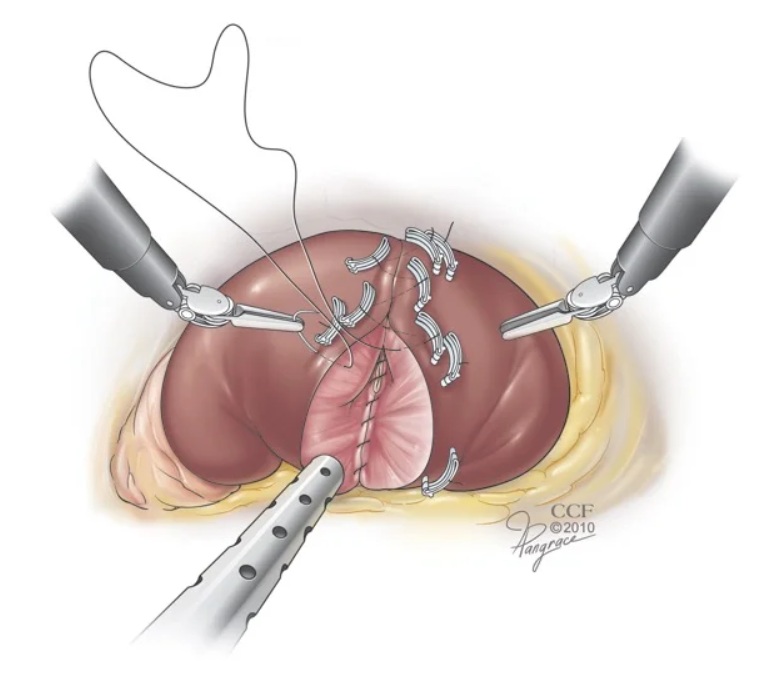

PROSTATECTOMIA ROBÓTICA

O tumor de próstata é o principal câncer que acomete ao homem, sendo de extrema importância o diagnóstico e tratamento precoces.

A PROSTATECTOMIA ROBÓTICA é uma técnica moderna e minimamente invasiva que utiliza uma plataforma robótica para melhorar a qualidade e precisão da cirurgia